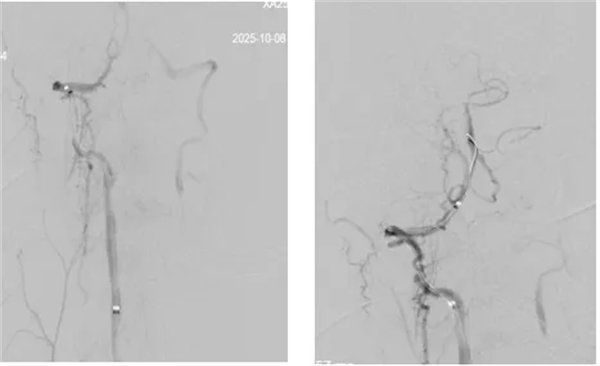

席聰準(zhǔn)確鎖定患者基底動(dòng)脈處血栓,采用抽吸取栓技術(shù)快速開(kāi)通血管,成功取出堵塞部位2cm的血栓。再次造影示:右側(cè)大腦后及雙側(cè)小腦上動(dòng)脈再通,右側(cè)大腦后動(dòng)脈P3段以遠(yuǎn)閉塞,考慮慢性閉塞,推注替羅非班,血流明顯加快。隨后采用支架植入術(shù)開(kāi)通右側(cè)椎動(dòng)脈開(kāi)口處,術(shù)中影像顯示:支架貼壁良好,無(wú)明顯殘余狹窄,顱內(nèi)血管顯影良好。